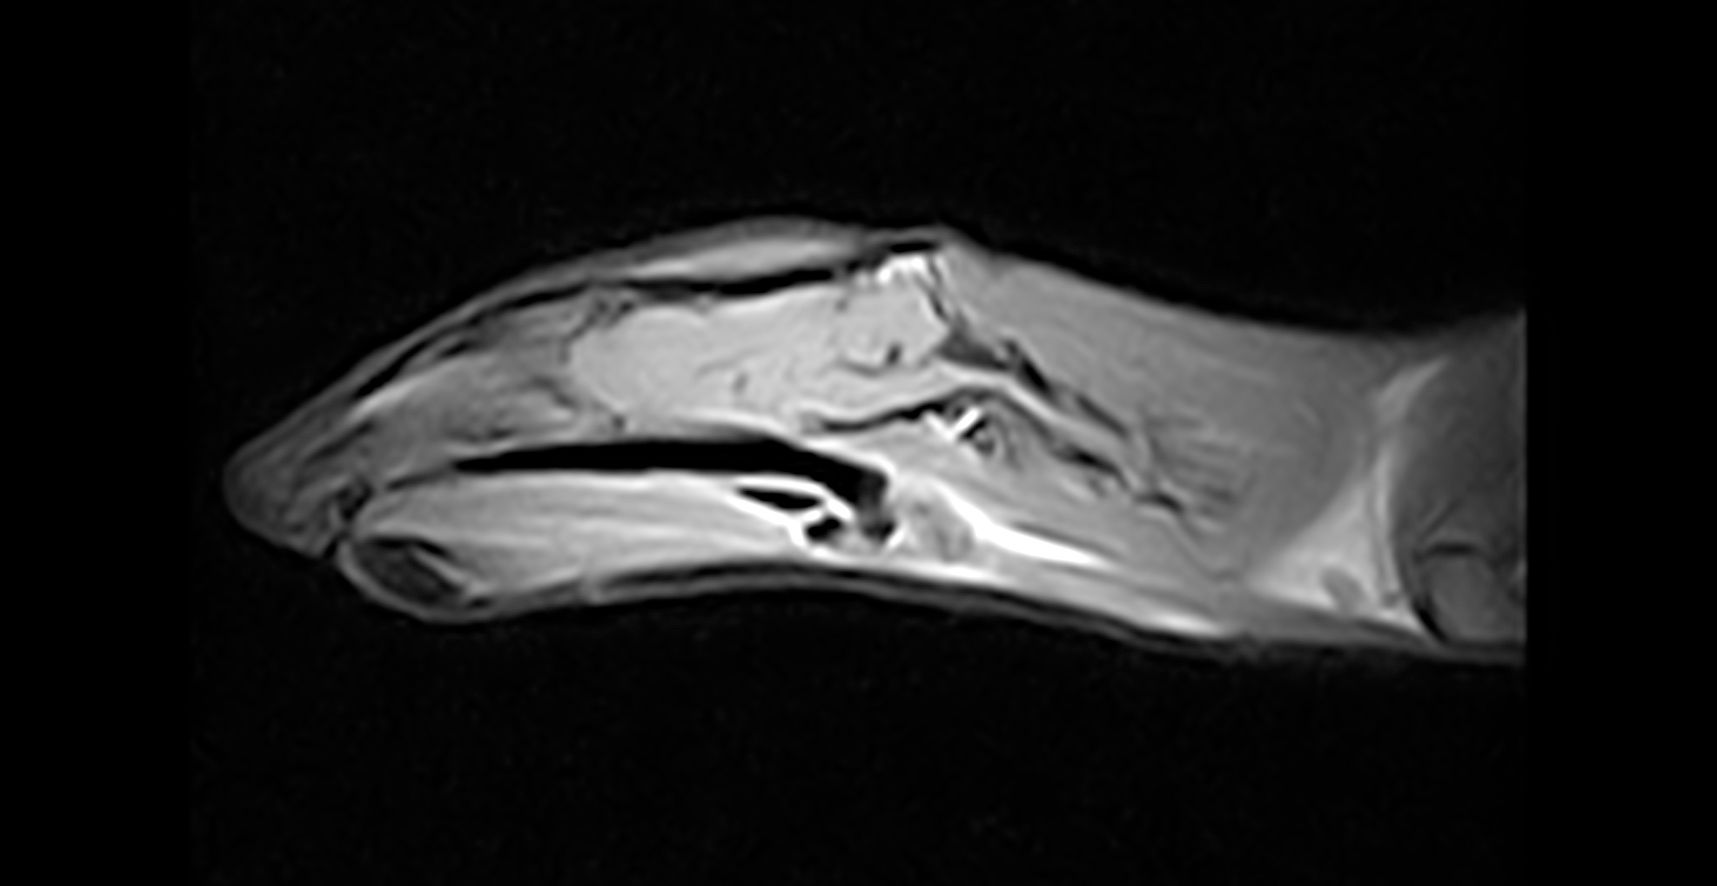

Maladie neurologique

Les maladies neurologiques chez les furets sont dominées par des troubles de type convulsions ou épilepsie, des paralysies de l'arrière-train ou des syndromes vestibulaires.

Il existe de nombreuses particularités chez le furet comparé aux carnivores domestiques. Les causes tumorales (insulinome et lymphome) sont très prédominantes mais des maladies rares (myasthénie, botulisme,etc...) sont également possibles.

Le diagnostic neurologique requiert des examens très spécifiques tels que la ponction de liquide céphalorachidien, l'IRM ou le scanner, le myéloscanner ou l'electromyographie/electroneurographie.